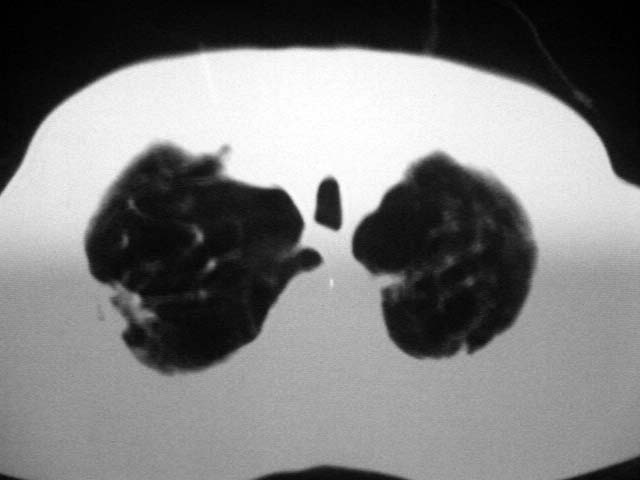

以下是引用zjzjr在2007-9-4 17:00:00的发言:[br]双上肺继发型结核伴左上肺空洞形成.慢性支气管炎伴肺气肿.

以下是引用liuzheng_9326在2007-9-4 16:23:00的发言:[br]痰检未见结核菌, 治疗后症状好转。图像符合陈旧性结核伴感染。